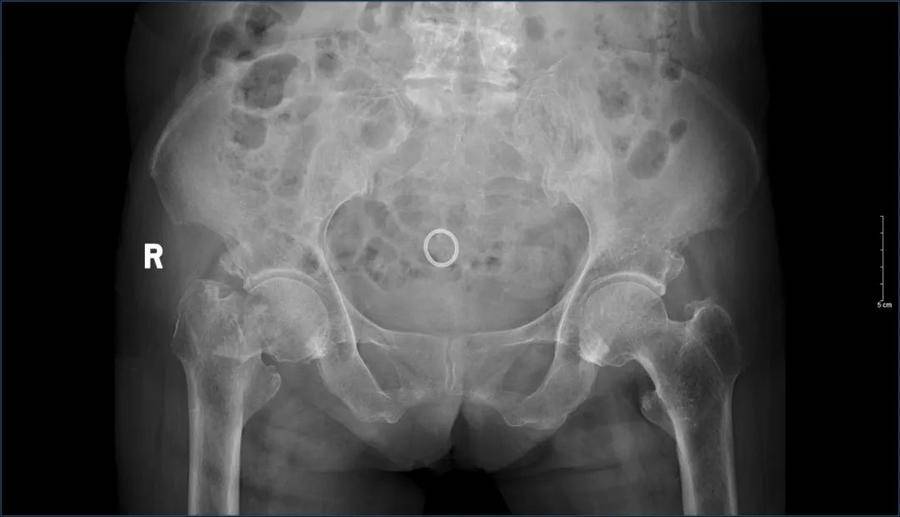

据了解,患者因不慎摔倒,在当地医院进行骨盆MRI检查后发现右侧股骨颈骨折,为进一步治疗,来到济南南郊医院就诊。经全面检查患者右股骨颈骨折,心功能不全,双上肢及双下肢静脉血栓形成,脑内多发缺血变性梗死灶,动脉硬化性脑白质病,脑萎缩,高血压等基础疾病。